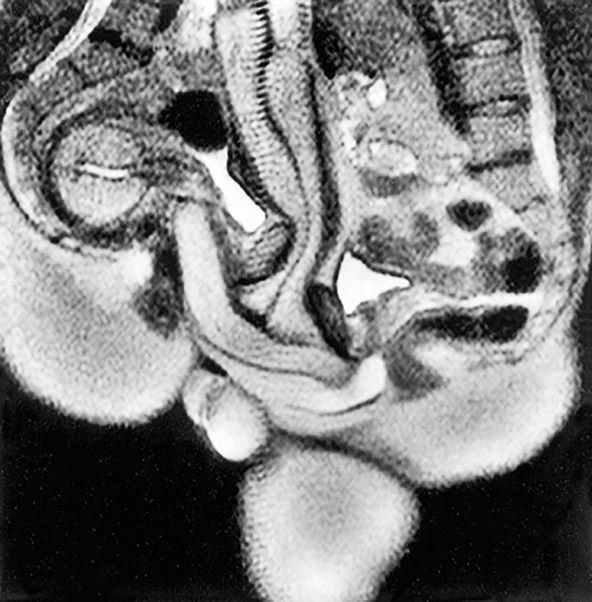

"To je poza koja za mene gotovo da ne izaziva uzbuđenje", rekla je ona, nakon čega u skeneru završili u "kašika" pozi. Kasnije, 1999. godine u "British Medical Journal" sprovedena je detaljnija studija koju i dalje čitaju hiljade ljudi svakog meseca. Jedan od najupečatljivijih nalaza iz eksperimenta bio je da ženska vagina nije samo prav tunel.

Dugo je postojalo verovanje da muški penis ulazi ravno u vaginu i izlazi isto tako napolje. Time se vodio i slikar Leonardo da Vinči koji nekoliko vekova ranije, tačnije 1492. godine, na crtežima prikazao vaginu kao prav cilindar.

Ali magnetna rezonanca je pokazala da "penis ima oblik bumeranga", što znači da se savija prema obliku tela žene, bez ikakvog bola za muškarca tokom njegove erekcije. Nakon Ide i Jupa, kasnije je sprovedeno još nekoliko eksperimenata intimnog odnosa u magnetnoj rezonanci. U pitanju su bili dobrovoljci stariji od 18 godina koji su mogli da odustanu u bilo kom trenutku. Kako je Ida istakla tokom svojevremenog intervjua, niko osim nje i Jupa nije mogao da završe test bez upotrebe vijagre.